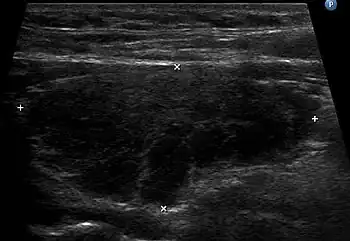

The thyroid of someone with Hashimoto's thyroiditis as seen with a microscope at low magnification

Gross morphological changes within the thyroid are seen in the general enlargement, which is far more locally nodular and irregular than more diffuse patterns (such as that of hyperthyroidism). While the capsule is intact and the gland itself is still distinct from surrounding tissue, microscopic examination can provide a more revealing indication of the level of damage.[24]